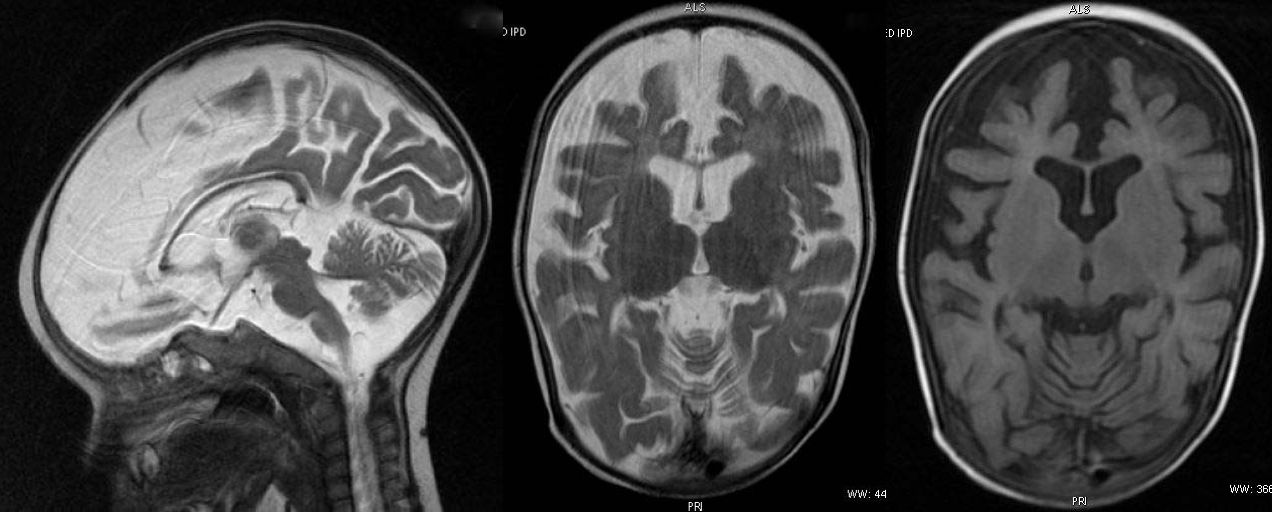

T2W axial, sagittal and axial FLAIR sequence revealing significant diffuse atrophy and reduced volume of corpus callosum. Prominence of sylvian fissure and CSF spaces noted. Mild cerebellar atrophy is appreciable in sagittal T2W image.

Non specific cerebral atrophy of different grades was observed in all cases except one. In [Table/Fig-2], reduced thickness of corpus callosum was observed in six patients on MRI brain studies. ITS cases who had severe wasting, three out of four showed evidence of cerebral atrophy; all three children with moderate wasting had evidence of cerebral atrophy. Cerebral atrophy was observed in all children with stunting as well as in children having normal height for age and sex. Some patients (6/10) had mild to moderate ventricular dilatation and most patients (9/10) had prominence of Sylvian sulcus. Ventricular dilatation and prominence of Sylvian sulcus had correlation with the grades of cerebral atrophy in all cases [Table/Fig-3,4,5,6,7,8,9,10,11 and 12].